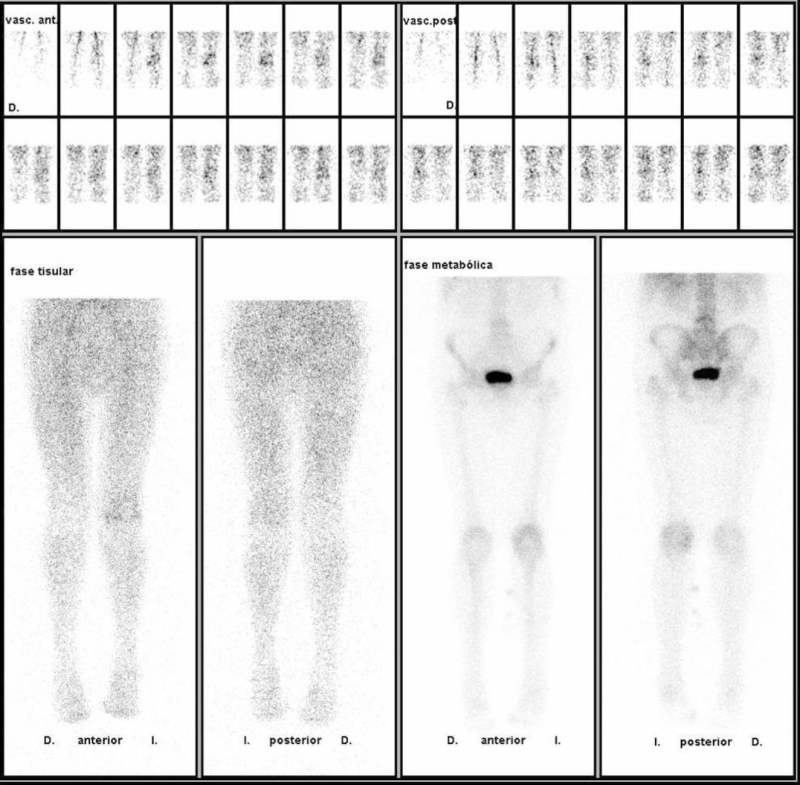

Se llevó a cabo un estudio combinado óseo con 99mTc-HMDP en tres fases y leucocitos marcados con 111In-Oxina con imágenes a las 4, 24 y 48 horas centradas en rodillas. Los hallazgos de la gammagrafía ósea (fig. 1) fueron interpretados como patología osteoarticular degenerativa asociada a cierto componente inflamatorio, sin datos gammagráficos característicos de infección. En las imágenes realizadas a las 4 horas con radioleucocitos no se observaron focos de hipercaptación patológicos. Sin embargo, en las imágenes de 24 y 48 horas se apreciaron pequeños acúmulos superficiales de radioreucocitos en ambas rodillas, que no se visualizaban en las imágenes precoces (fig. 2).

Ante los hallazgos de estas últimas imágenes se examinó al paciente, objetivándose la presencia de lesiones telangiectásicas en ambas extremidades inferiores (fig. 3), donde los radioleucocitos se habían acumulado debido probablemente a la propia estasis venosa.